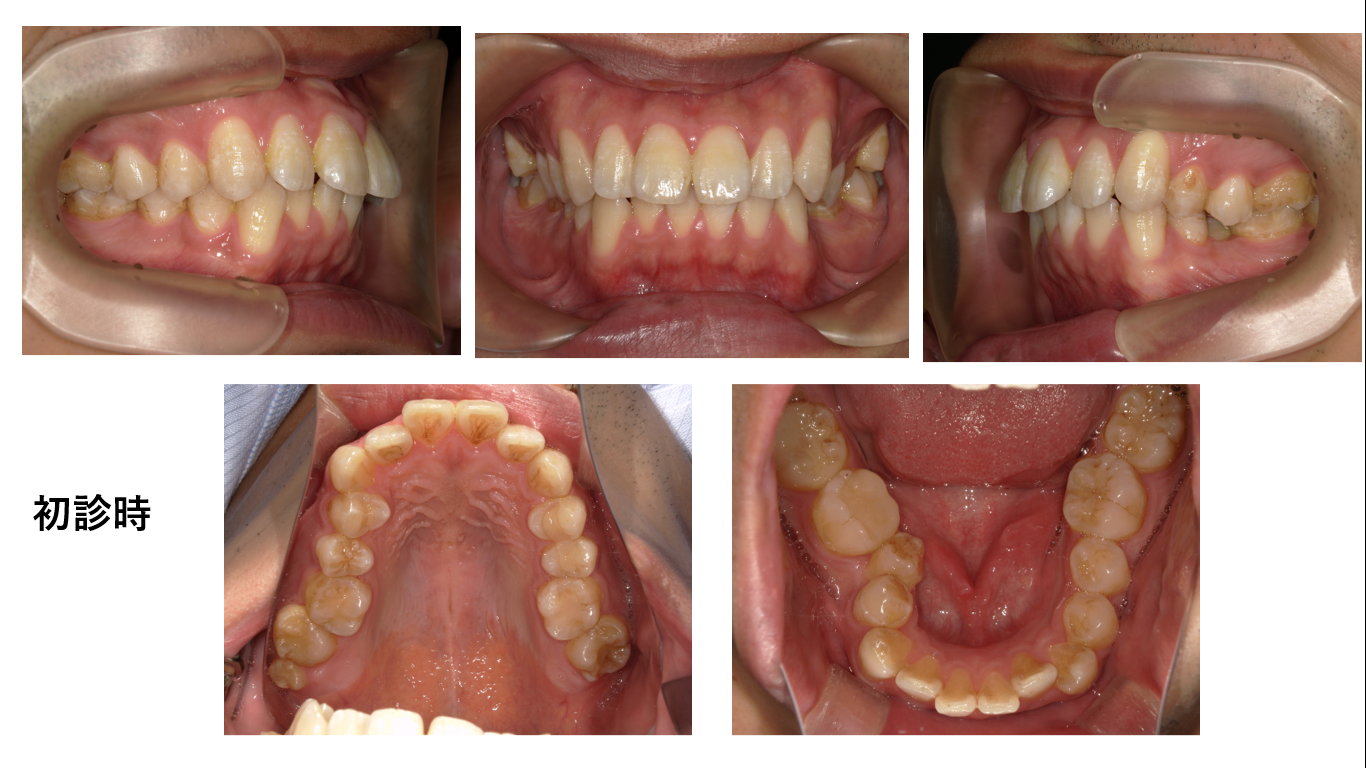

矯正症例 140 AngleⅠ級上下顎前突、舌側矯正,口ゴボ,裏側矯正

治療開始年齢29歳3か月、治療期間3年3か月、抜歯部位:上下顎左右4番、下顎左右8番、上顎右側8番、治療費総額¥1,580,000(税込み)口蓋正中部にアンカースクリュー除去の跡があることでわかる通り...